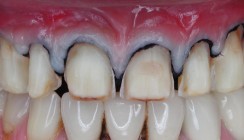

Klinischer Befund – rote Ästhetik

Hinweis: Die Aufnahmen der Lateral- und Okklusalansicht wurden gespiegelt, um eine seitenrichtige Darstellung wiederzugeben (Zustand nach Sanierung im SZB). Die Bilder wurden am 10. Juli 2008 mit einer Canon EOS 300D und einem Canon Macro Lens EF 100mm 1:2,8 Objektiv aufgenommen. Im Ober- und Unterkiefer sind ein regelmäßiger Gingivasaum sowie wohlgeformte Interdentalpapillen zu erkennen (Abb. 1). Ferner liegt ein Biotyp mit dünner Gewebestärke vor. Die Patientin verfügt über eine kurze und schmal geformte Oberlippe (Abb. 3). Beim Lächeln zeigt sich eine leichte Asymmetrie rechts, welche aber dezent erscheint und die Patientin nicht stört. Es liegt eine mittelhohe Lachlinie vor.